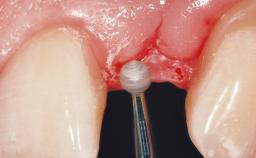

Late Flapless Placement of an Implant in a Maxillary Left Central Incisor Site

A 39-year-old male patient presented with a chief complaint of discomfort and gingival discoloration around his maxillary left central incisor. He was in good general health and was a non-smoker. His past dental history was significant because of the traumatic fracture of tooth 21 in a sporting accident at age 13. Initial dental treatment included endodontic therapy and a full-coverage restoration. The patient became symptomatic 5 years later, when structural failure of the tooth resulted in the dislodgment of the crown. Endodontic retreatment, apical surgery, and post-and-core restoration were performed.

Soft Tissue Grafting Simultaneous

Bone Volume Deficient horizontally, requiring prior grafting